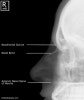

6) Adult Facial Bones - Lateral View